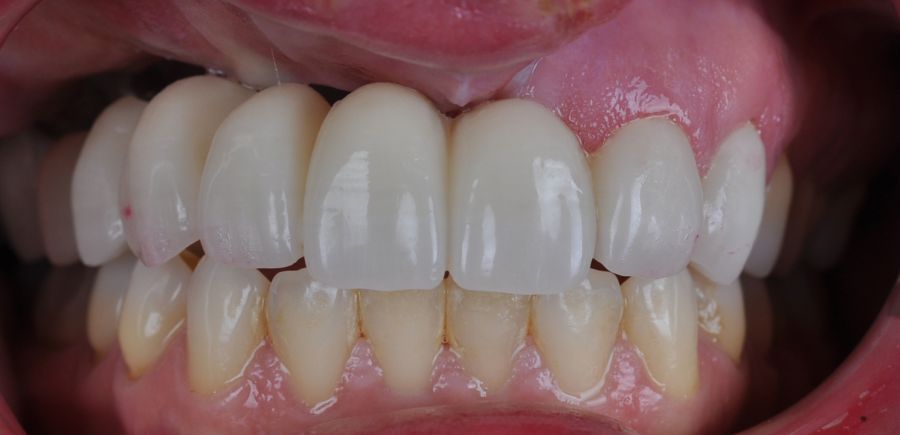

El día de la colocación de las estructuras, se arenó el interior de las coronas dentosoportadas con óxido de aluminio de 50 m y fueron cementadas con cemento de resina Multilink Ò. El puente implantosoportado se atornilló al torque indicado (20Nw) (Figuras 14, 15, 16 y 17).

Las impresiones analógicas y el posterior flujo digital permitieron una correcta planificación protésica. Las estructuras definitivas, confeccionadas en óxido de zirconio monolítico sobre interfases metálicas de titanio, mostraron una adecuada adaptación pasiva tanto clínica como radiográficamente. La prueba estética permitió ajustes oclusales y funcionales mínimos, optimizando el resultado final.

En enero de 2021, el puente implantosoportado fue atornillado con un torque controlado (20 Nw), y las coronas dentosoportadas cementadas con éxito. La paciente refirió una notable mejoría en la función masticatoria, fonación y estética facial, manifestando un alto grado de satisfacción.

En el seguimiento a 4 años tras la colocación de la prótesis definitiva, no se observaron complicaciones mecánicas ni biológicas. La paciente continúa libre de enfermedad y con una correcta adaptación al tratamiento rehabilitador implantosoportado (Figura 18).